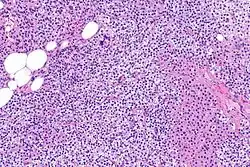

Parathyroid glands are normally composed of chief cells, adipocytes and scattered oxyphil cells.[27][14] Chief cells are thought to be responsible for the production, storage and secretion of parathyroid hormone. These cells appear light and dark with a prominent Golgi body and endoplasmic reticulum. In electron micrographs, secretory vesicles can be seen in and around the Golgi and at the cell membrane. These cells also contain prominent cytoplasmic adipose.[27][14] Upon onset of hyperplasia these cells are described as having a nodular pattern with enlargement of protein synthesis machinery such as the endoplasmic reticulum and Golgi. Increased secretory vesicles are seen and decreased intercellular fat is characteristic.[27][24] Oxyphil cells also appear hyperplasic however, these cells are much less prominent.

Biochemically, there are changes in function between normal and nodular hyperplastic parathyroid glands. These changes involve proto-oncogene expression and activation of proliferative pathways while inactivating apoptotic pathways.[28] In nodular parathyroid tissue increased expression of TGF-a, a growth factor, and EGFR, its receptor, results in aggressive proliferation and further downregulation of vitamin D receptors, which act to suppress hormone secretions.[25][8][28] Furthermore, the proliferative marker, Ki67 is seen to be highly expressed in the secondary nodular hyperplastic state.[28][25] Tumour suppressor genes have also been highlighted as being silenced or degraded in nodular hyperplastic parathyroid tissue.[8][28] One such gene, p53, has been shown to regulate multiple tumour suppressor pathways and in tumorigenesis can be degraded by b-catenin. This pathway, in some aspect, is mediated by CACYBP, which is highly expressed in nodular parathyroid hyperplasia.[28]